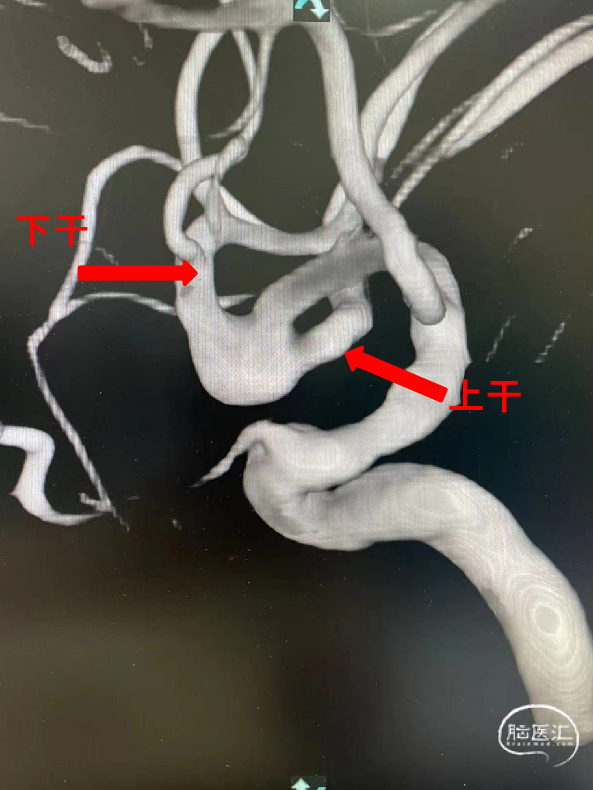

术前三维测量显示瘤体大小,瘤体约8.16mm*3.27mm,累及上下干, 上干约2.43mm,下干约3.56mm。

该例动脉瘤位于MCA分叉部,位置正好位于分叉部中间,几乎平均累及MCA两干。如采用单支架辅助致密栓塞,没有支架保护的另一干有较高的血栓风险。

MCA的两干(尤其是上干),与M1水平段的夹角角度刁钻,预期微导管超选有困难。治疗策略上计划先在上下两干均提前预置支架导管留作保障,防止一枚支架释放后钻支架网眼不能超选入另一干,这样预置的微导管可以释放另一枚Atlas支架,作为备选方案。